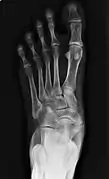

Radiological images

Type 2 on one foot (dark arrow) and type 3 on the other (white arrow)